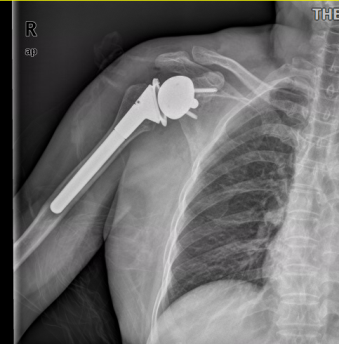

薛恩兴副主任医师在美国进修期间掌握反球型人工肩关节置换术(简称反肩关节置换手术)。因此经反复讨论研究及与患者沟通,最终决定选择克服困难,为其实施该手术。

反式肩关节置换术是一项复杂、技术难度较高的手术。反肩关节置换手术原理是通过将肱骨头与肩胛盂的球臼接触关系面反转调换,从而将肩关节旋转中心内移,以此增加三角肌力臂,并增加三角肌的力矩,由此来替代肩关节启动外展时肩袖所提供的下压肱骨头作用,以帮助上臂完成外展动作。因此主要适用于伴有肩袖功能缺失的肩关节骨性关节炎老年患者。它不同于传统的肩关节置换术,具有更广泛的临床疗效。

经过精心准备,我院骨科薛恩兴副主任医师团队成功完成我院首例反肩关节置换手术。通过反球型人工肩关节置换,解除了困扰患者长达一年的病痛。患者术后6天出院。术后4周门诊随访,恢复良好,并表示对疗效满意。

反式肩关节置换术作为老年性肩关节疾病的有效治疗手段在欧美等国家已经开展20余年,国内则处于引进起步阶段,目前浙江省仅少数医院开展,温州地区尚属首例。